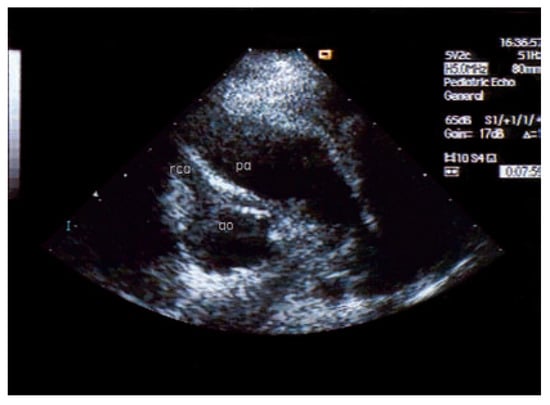

An otherwise healthy 13-year-old girl was referred to the pediatric cardiology outpatient clinic for evaluation of a newly observed systolic murmur. She was normally physically active without symptoms on exertion except for one episode of syncope two months earlier. She then was riding a bike and on climbing off the bike she was observed to hyperventilate, had parestesias of both hands followed by a short loss of consciousness. Family history was negative for any cardiac event. Clinically the systolic murmur was judged a functional ejection murmur but an Echo was done and revealed an enlarged (6 mm) right coronary artery (Figure 3) with huge collaterals especially in the septal region (Figure 4), the origin of the left coronary artery was seen in the pulmonary trunk with turbulent retrograde flow in the color Doppler (Figure 5). LV ejection fraction was 68% but the LV was slightly dilated with a mild mitral regurgitation. Cardiac catheterisation confirmed the suspected anomalous origin of the left coronary artery from the pulmonary trunk (Figure 1 and Figure 2), the patient was advised to undergo surgical correction with reimplantation of the left coronary artery in the aorta.

Figure 1. Anteroposterior view of aortography: late phase still shows dilated RCA with tortuous course and retrograde flow through the left coronary artery with drainage into the pulmonary artery.